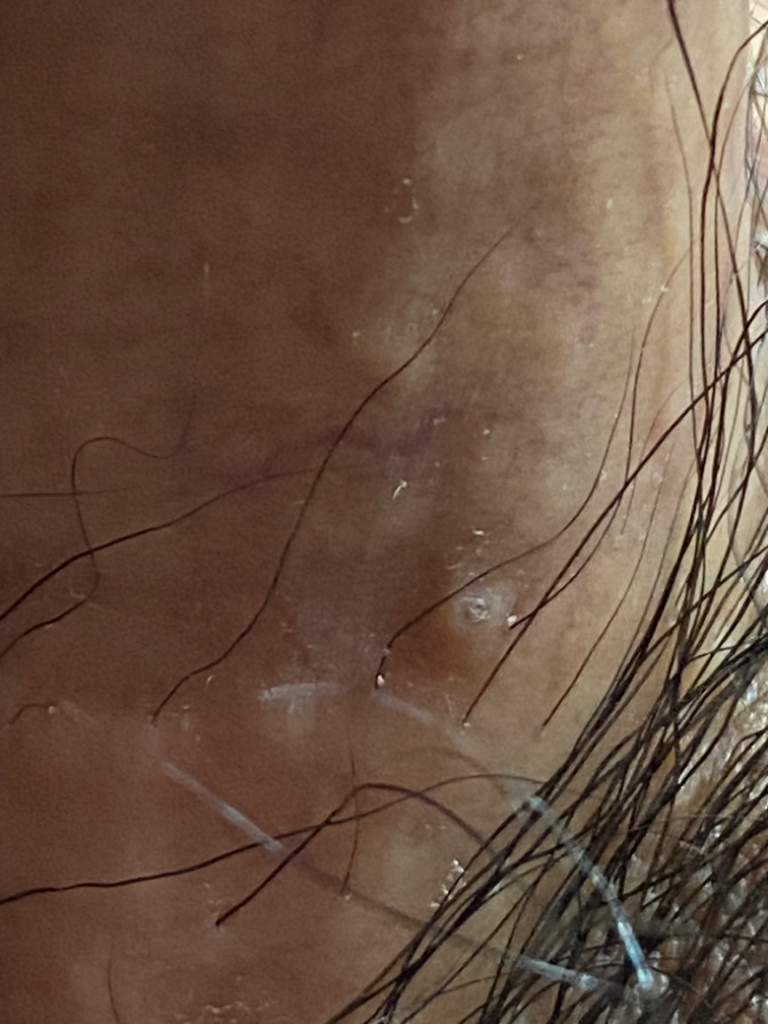

이거 곤지름인가요? 가려움증은 없습니다

곤지름일까요 궁금해서 질문 남거드립니다 크기는 좁쌀여드름만한 크기 입니다 답변좀 꼭 부탁드리겠습니다 의사선생님!!!!!!

• 1번 째 사진

곤지름 가능성이 높아보이는 병변은 아니나 증상이 지속되거나 퍼진다면 비뇨기과 방문해보시는 것을 권유 드립니다.